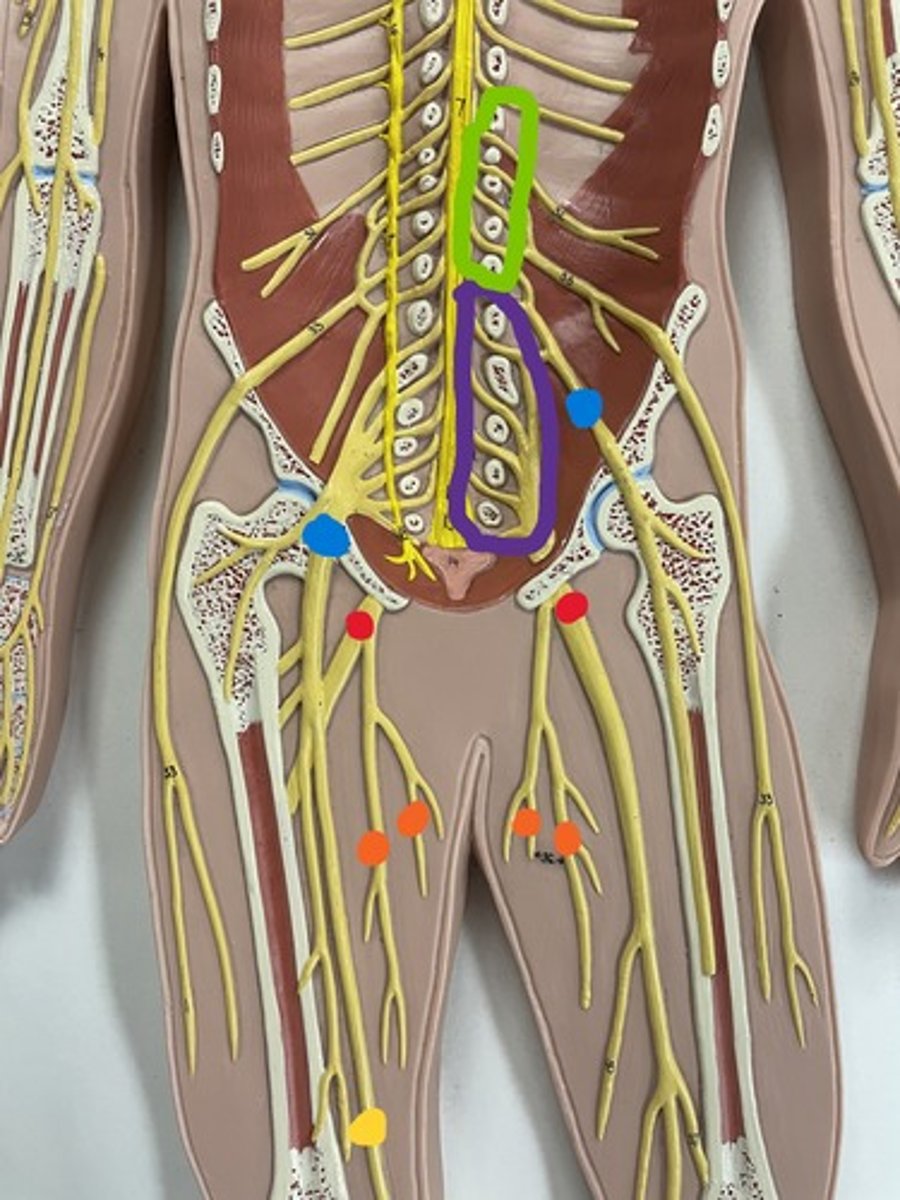

Lumbar plexus

Lumbar plexus

green

Femoral nerve

purple

Femoral nerve

blue

Obturator nerve

yellow

Obturator nerve

orange

Saphenous nerve

yellow

Sacral plexus

purple

Sacral plexus

red

Sciatic nerve

red

Tibial nerve

red

Common fibular nerve

blue